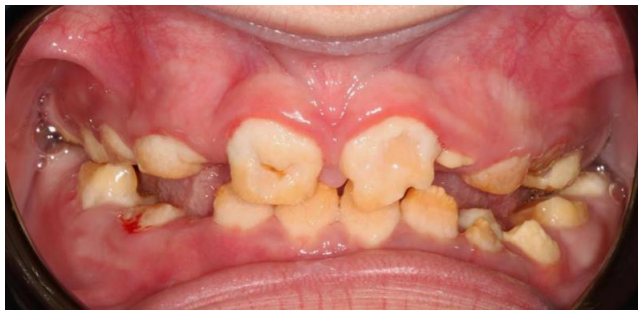

Oral (figure 1) and radiographic (figure 2) examination of the patient showed consistent dental findings: generalized, thin hypoplastic or absent enamel; both primary and permanent teeth affected; flat cusps on posterior teeth; relative microdontia and spaced teeth; delayed tooth eruption; impacted posterior teeth; and semi-lunar shape of central incisor edge. Hypomaturation or hypocalcified AI have never been described in ERS.1

Figure 1: Clinical presentation